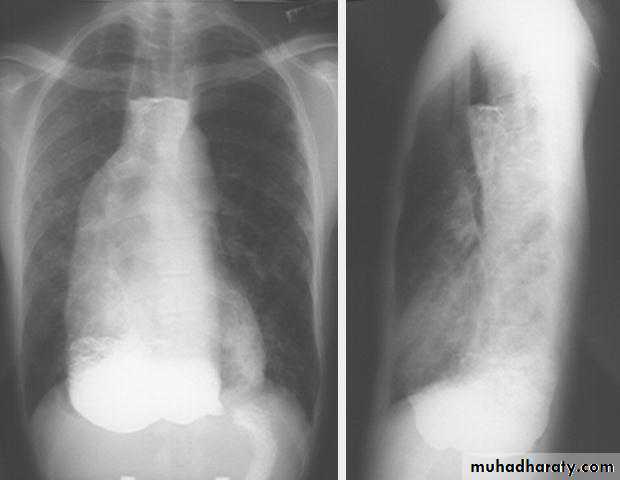

Chest X-ray: widening of the mediastinum, aspiration pneumonia.A barium swallow: tapered narrowing of the lower esophagus, esophageal body is dilated, aperistaltic and food-filled.

Long, smooth distal esophageal stricture as evidenced by lack of normal distension of the esophagus.